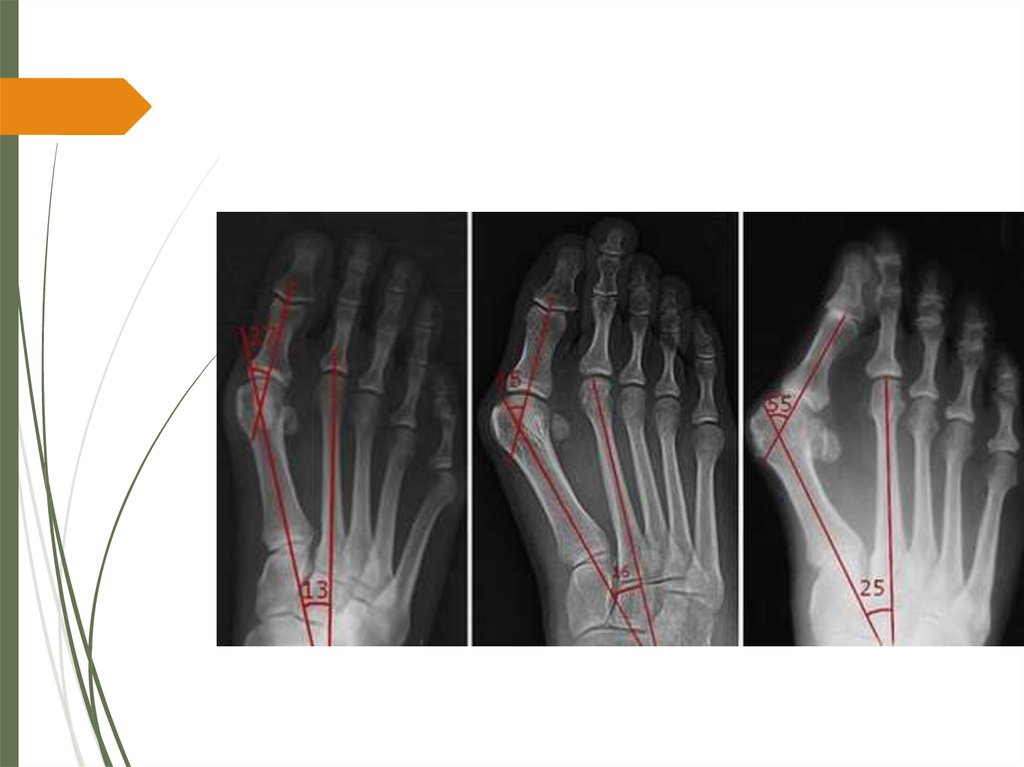

1. Первый межплюсневый угол – угол между

(рис. 1). В норме он составляет от 00 до 140 .

Увеличение значения этого угла обозначается как

metatarsus primus adductus.

2. Угол вальгусного отклонения первого пальца стопы –

угол, образованный референтными линиями первой

плюсневой кости и основной фалангой первого пальца

(Рис. 1). В норме он составляет менее 16 град.

Деформация характеризуется как слабая при угле от

16 до 25 гр., средняя при угле от 25 до 35 гр., и тяжелая

деформация с имеющимся подвывихом в первом

плюснефаланговом суставе при значении угла более

35 град.

3. Угол наклона дистальной суставной поверхности

первой плюсневой кости (PASA) – этот угол

формируется линией, проведенной параллельно

эффективной суставной поверхности и

перпендикуляром к референтной линии первой

плюсневой кости. В норме этот угол должен быть не

более 8 градусов (рис. 2).